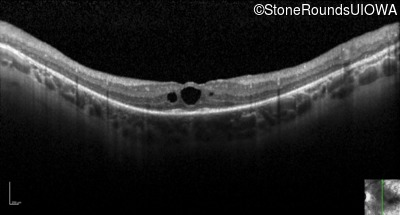

Optical Coherence Tomography - Right - 20/80 +2

Exemplar / OCT Stack